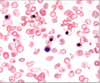

A

normal red blood cells